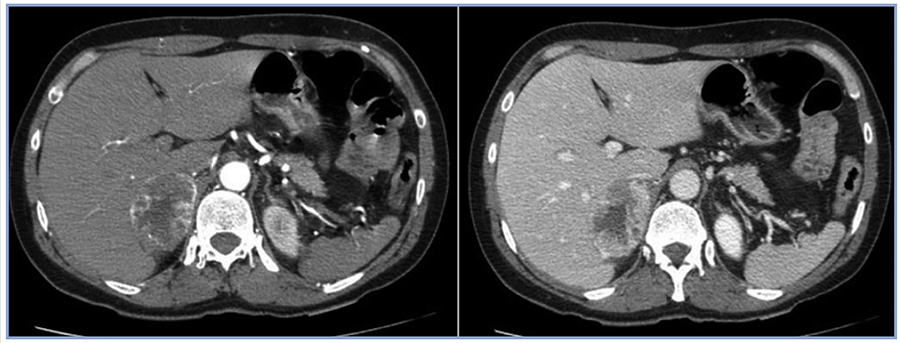

Consultó en urgencia por cuadro de dolor retroesternal de inicio agudo, opresivo, irradiado a dorso, diaforesis y palpitaciones. A su ingreso destaca: presión arterial (PA) 214/120 mmHg, frecuencia cardiaca (FC) 126 x min, mala perfusión, somnolencia y manchas café con leche. Las enzimas cardiacas mostraron valores normales. El ECG reveló supradesnivel de ST y T negativas de V2 a V4, con Q patológica en V5-V6-DI y AVL. Coronariografía: Coronarias sin lesiones, hipokinesia difusa con fracción de eyección (FE) de 20%. Interpretándose como miocardiopatía de Takotsubo (MTT) (Figura 1). En base a los hallazgos con alta sospecha de feocromocitoma, se solicita metanefrinas urinarias totales: 6,3 mg/24 h (VN: 0-1), TSH 2,32 uIU/ml PTH: 46,1 pg/ml Ca 9,5 mg/ dl, P: 4 mg/dl, Alb: 4,3g/dl Calcitonina basal: 4,8 pg/ml (VN: < 4). Ecografía renal descartó estenosis de arterias renales con masa renal sugerente de neoplasia. TC con contraste: masa suprarrenal derecha de 6,3 cm de eje mayor con características de feocromocitoma (Figura 2).

Figura 1. Coronariografía: Coronarias sin lesiones.